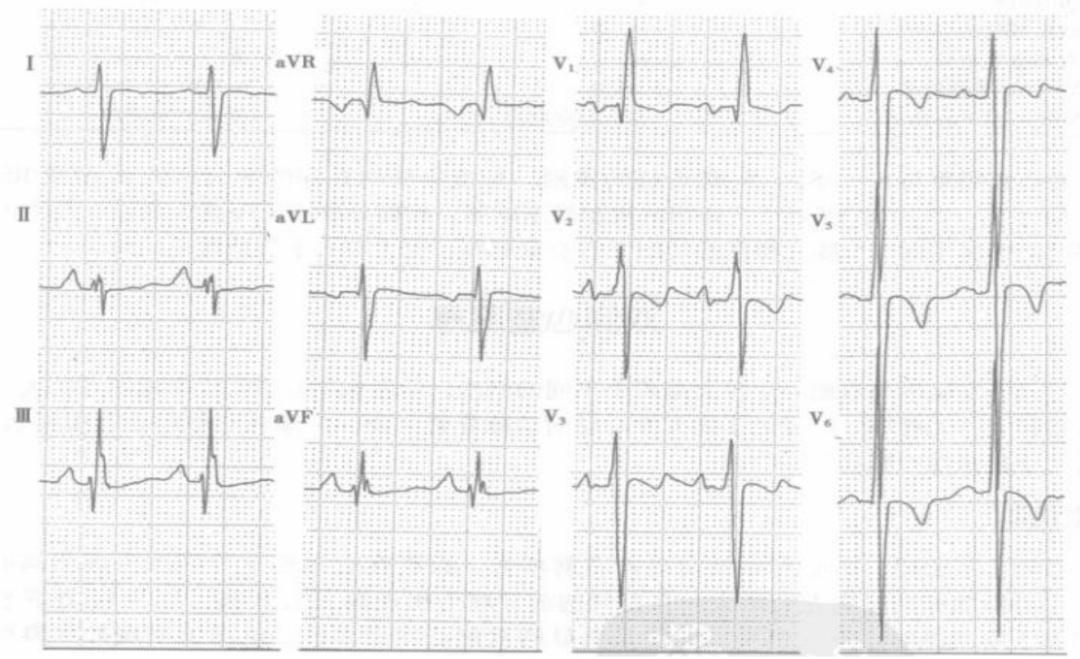

(4)一例右心室肥厚患者心电图

半电压下测量,RV1=22mm,电轴右偏,+110° ,V1-V4导联ST段压低,T波倒置